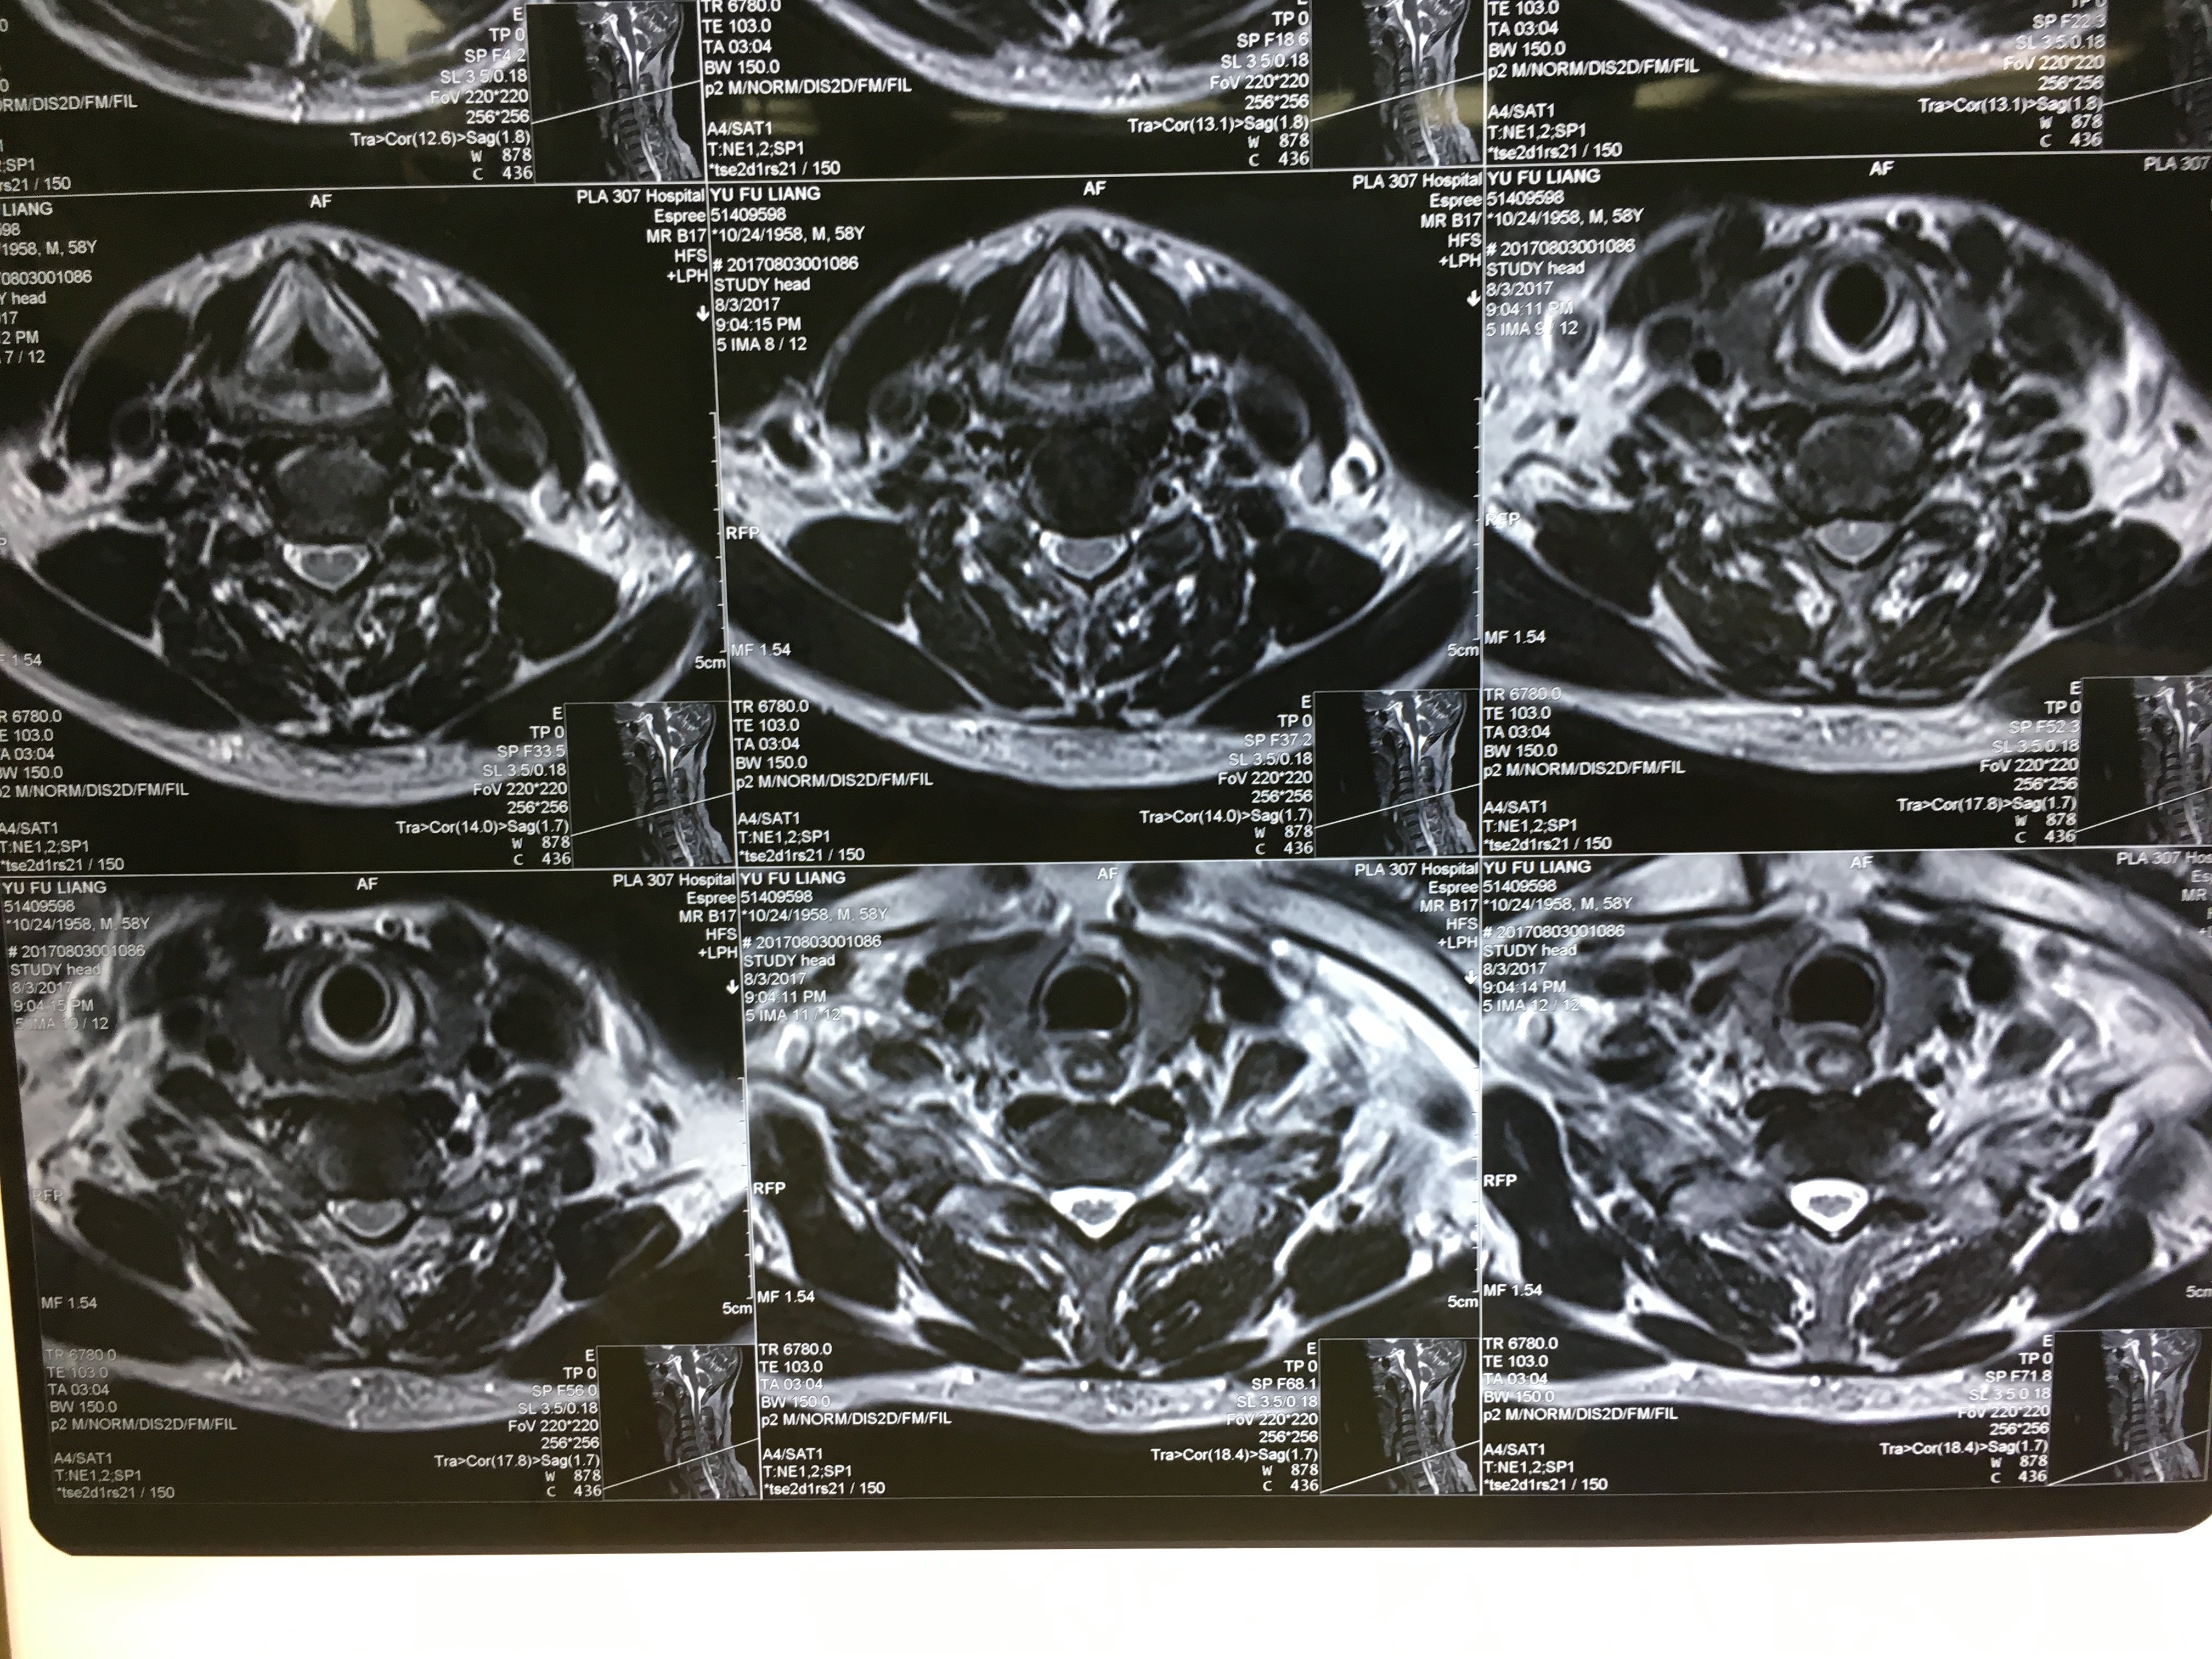

病例 Acdf手术治愈颈椎间盘突出一例 网易订阅